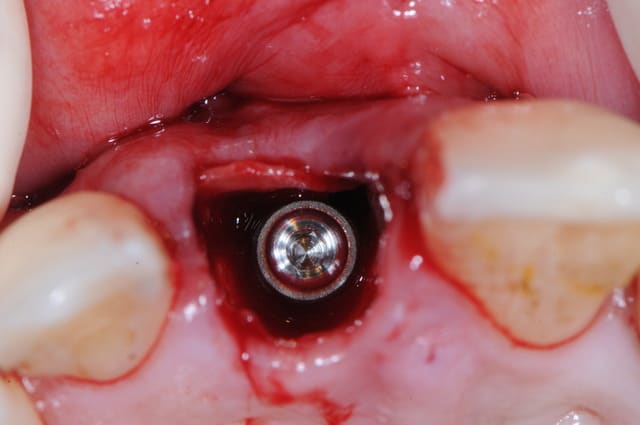

Je poste le cas en avant premiere ici.

C'est tout frais du mois dernier.

Le problème de faire comme ça c'est que tu positionnes ton implant au hasard. Tu fais une estimation de la position verticale de ton rebord osseux après cicatrisation.

Un coup ça marche, un coup ça marche pas. Tu peux très bien te retrouver avec un feston gingival absolument hideux.

La photo #4 montre l'implant en position finale ?

Oui, l'implant est en position finale sur la photo 4.